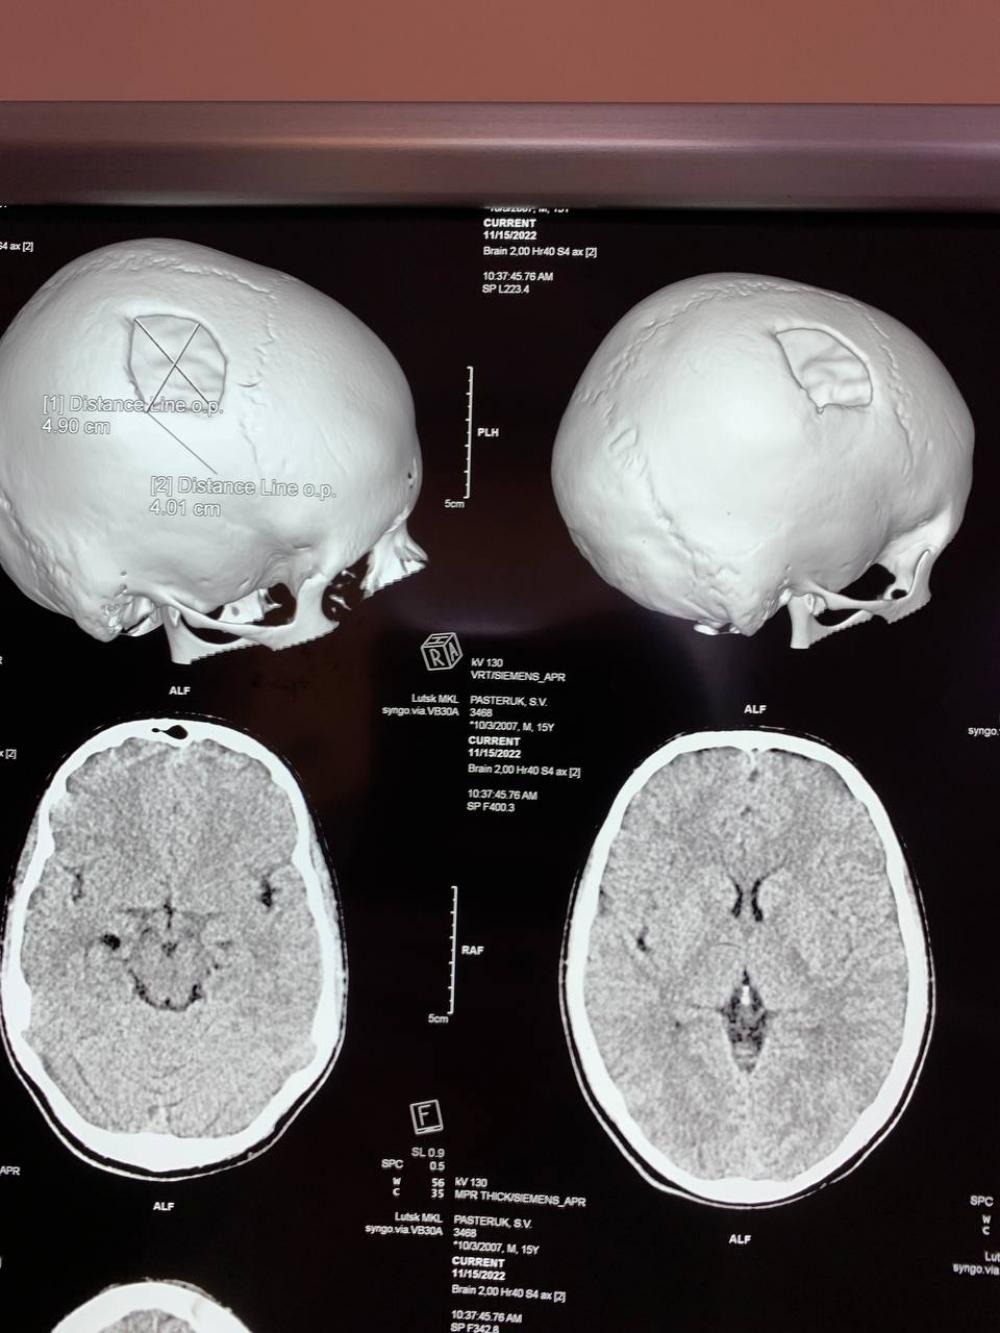

15-річний хлопець 9 місяців тому отримав складну черепно-мозкову травму. Тому днями йому виконали краніопластику.

"Пошкоджену частину черепної коробки закрили спеціальною титановою пластиною, яка повторює кісткові структури черепа та захищає мозок від ушкоджень", - розповіли лікарі.